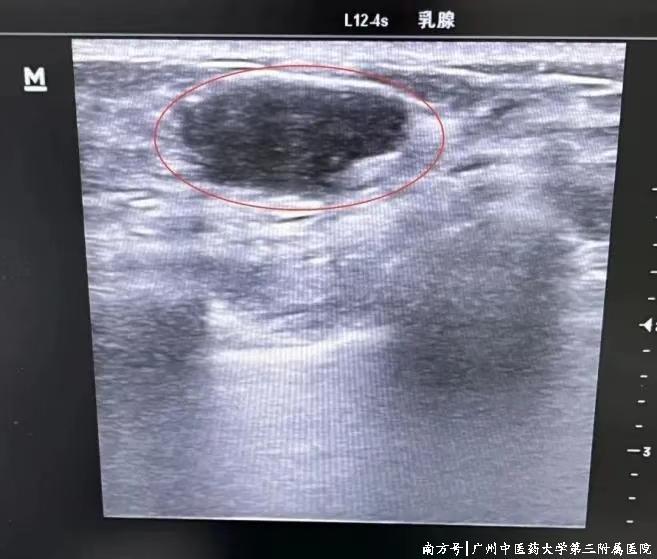

△B超下的乳腺结节

2.超声可见的可疑病灶活检:对于BI-RADS分类为4b及以上的可疑病灶,或4a类但结节较小或患者不接受开放手术的情况,微创旋切术可以提供准确的活检结果。无论病灶大小,微创旋切术都能提供足够的组织样本用于病理诊断。